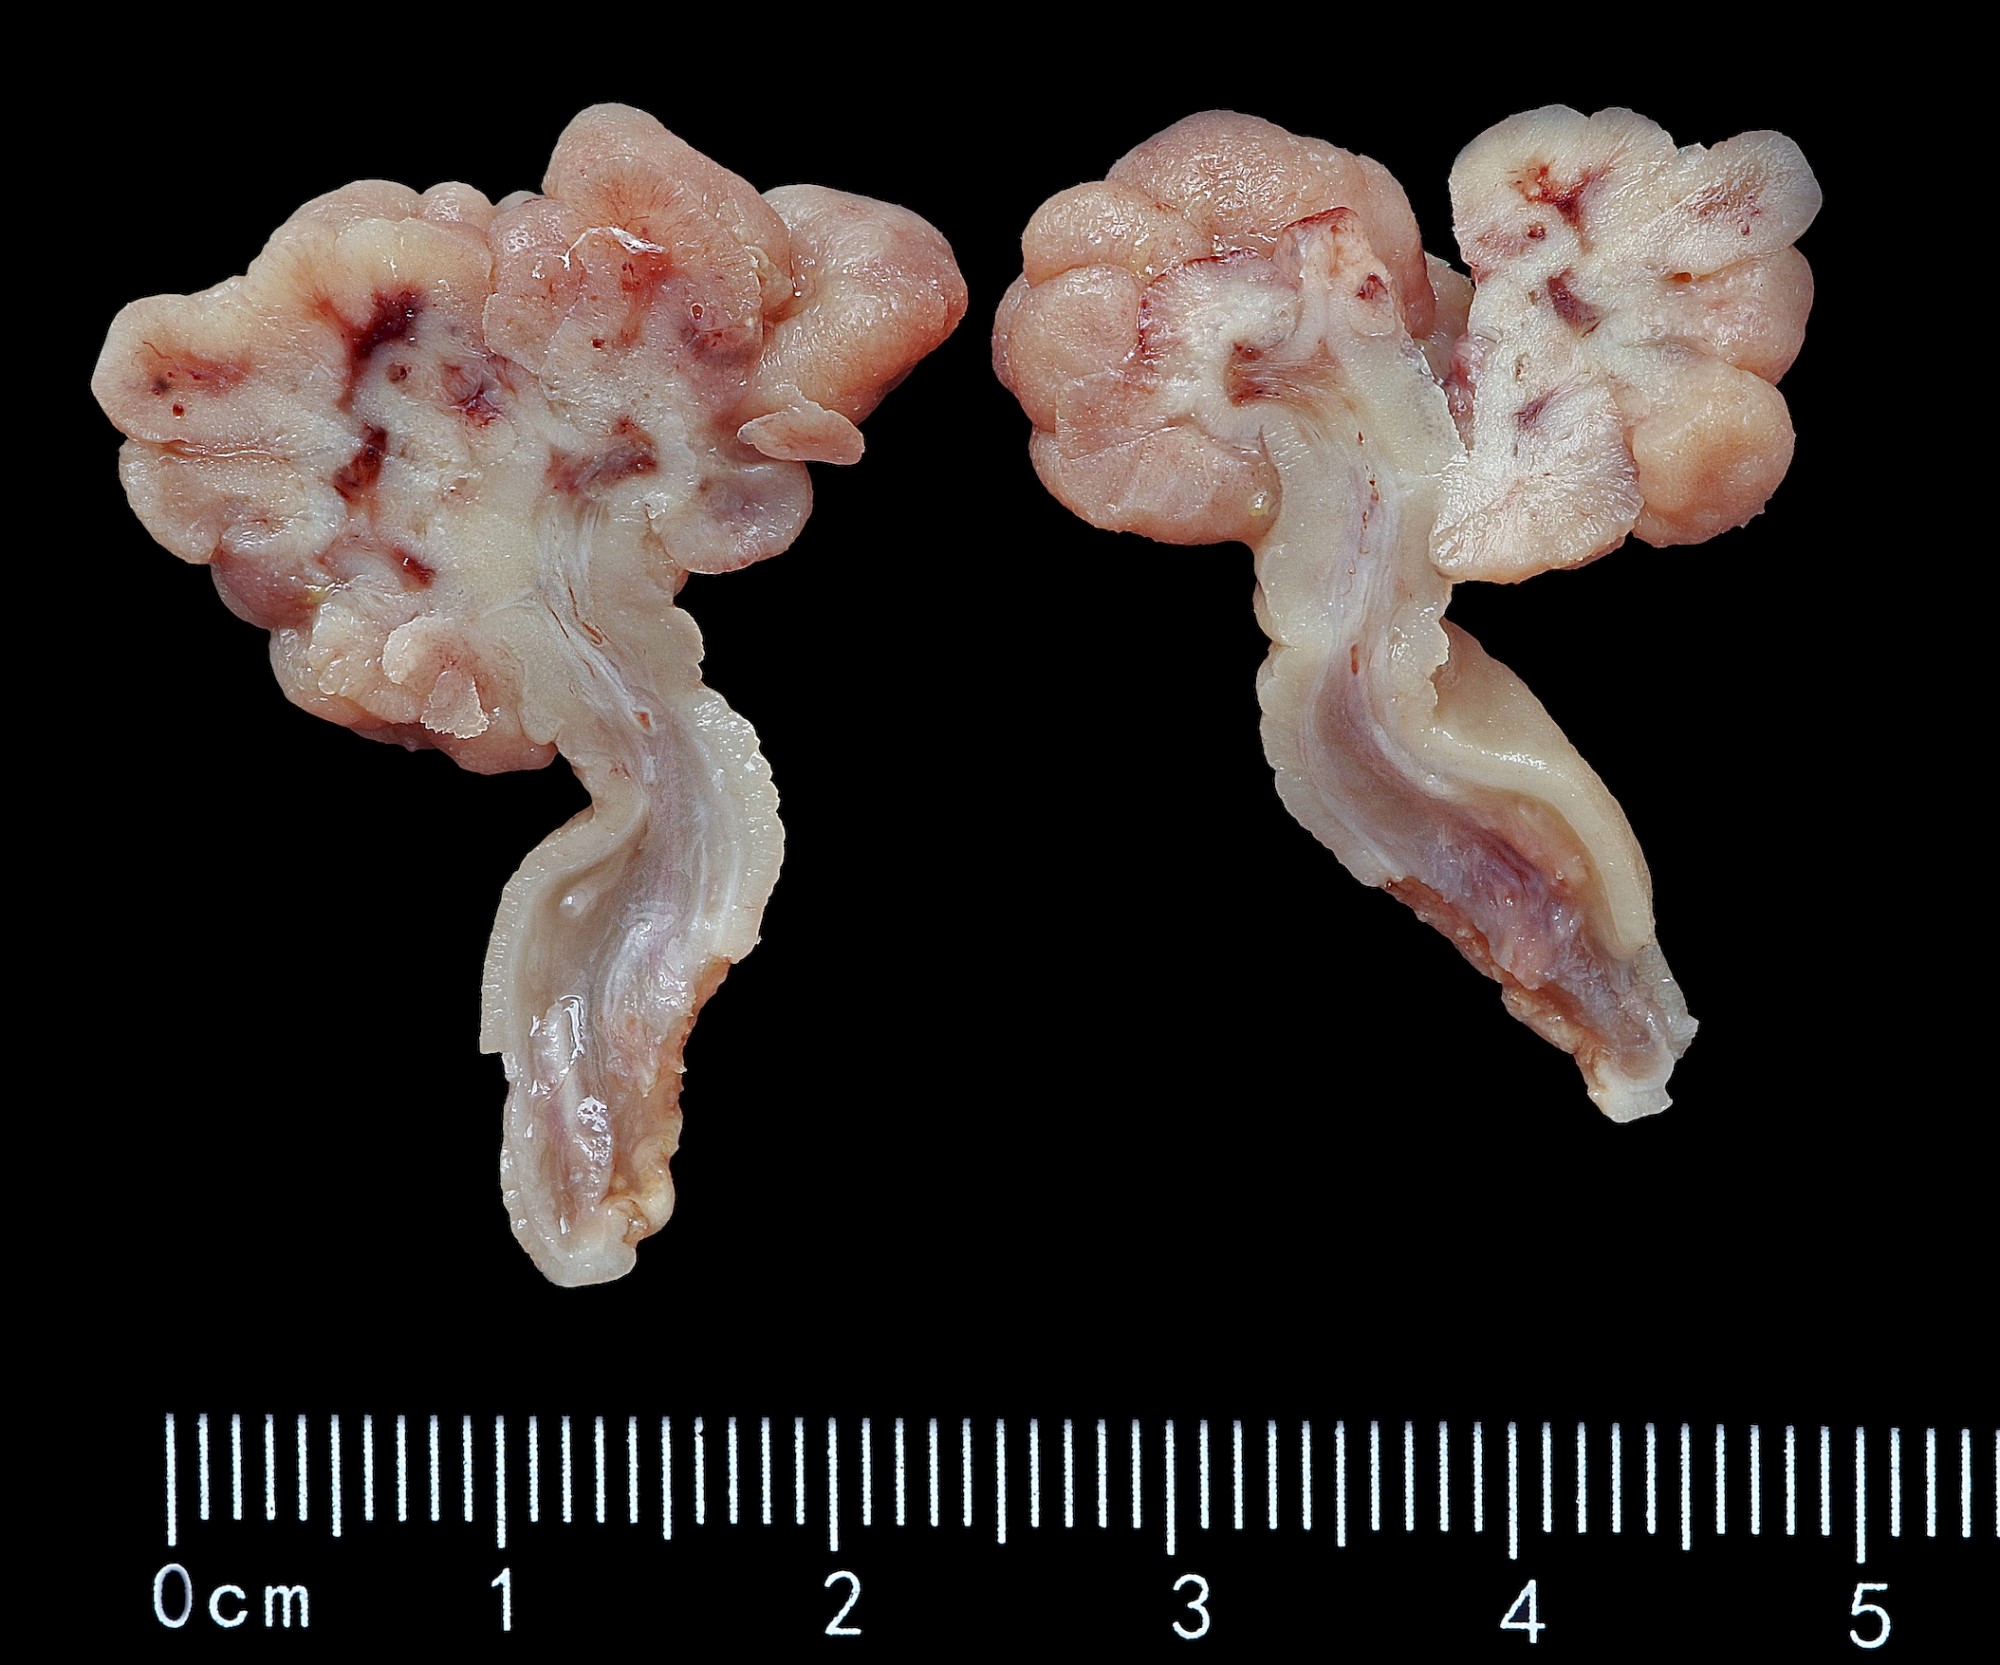

Gross description

- May be sessile or pedunculated

- Typically dark red compared with mucosa

- Features concerning for high grade dysplasia or malignancy include size > 1 cm, villous architecture and ulceration / friability

Gross images